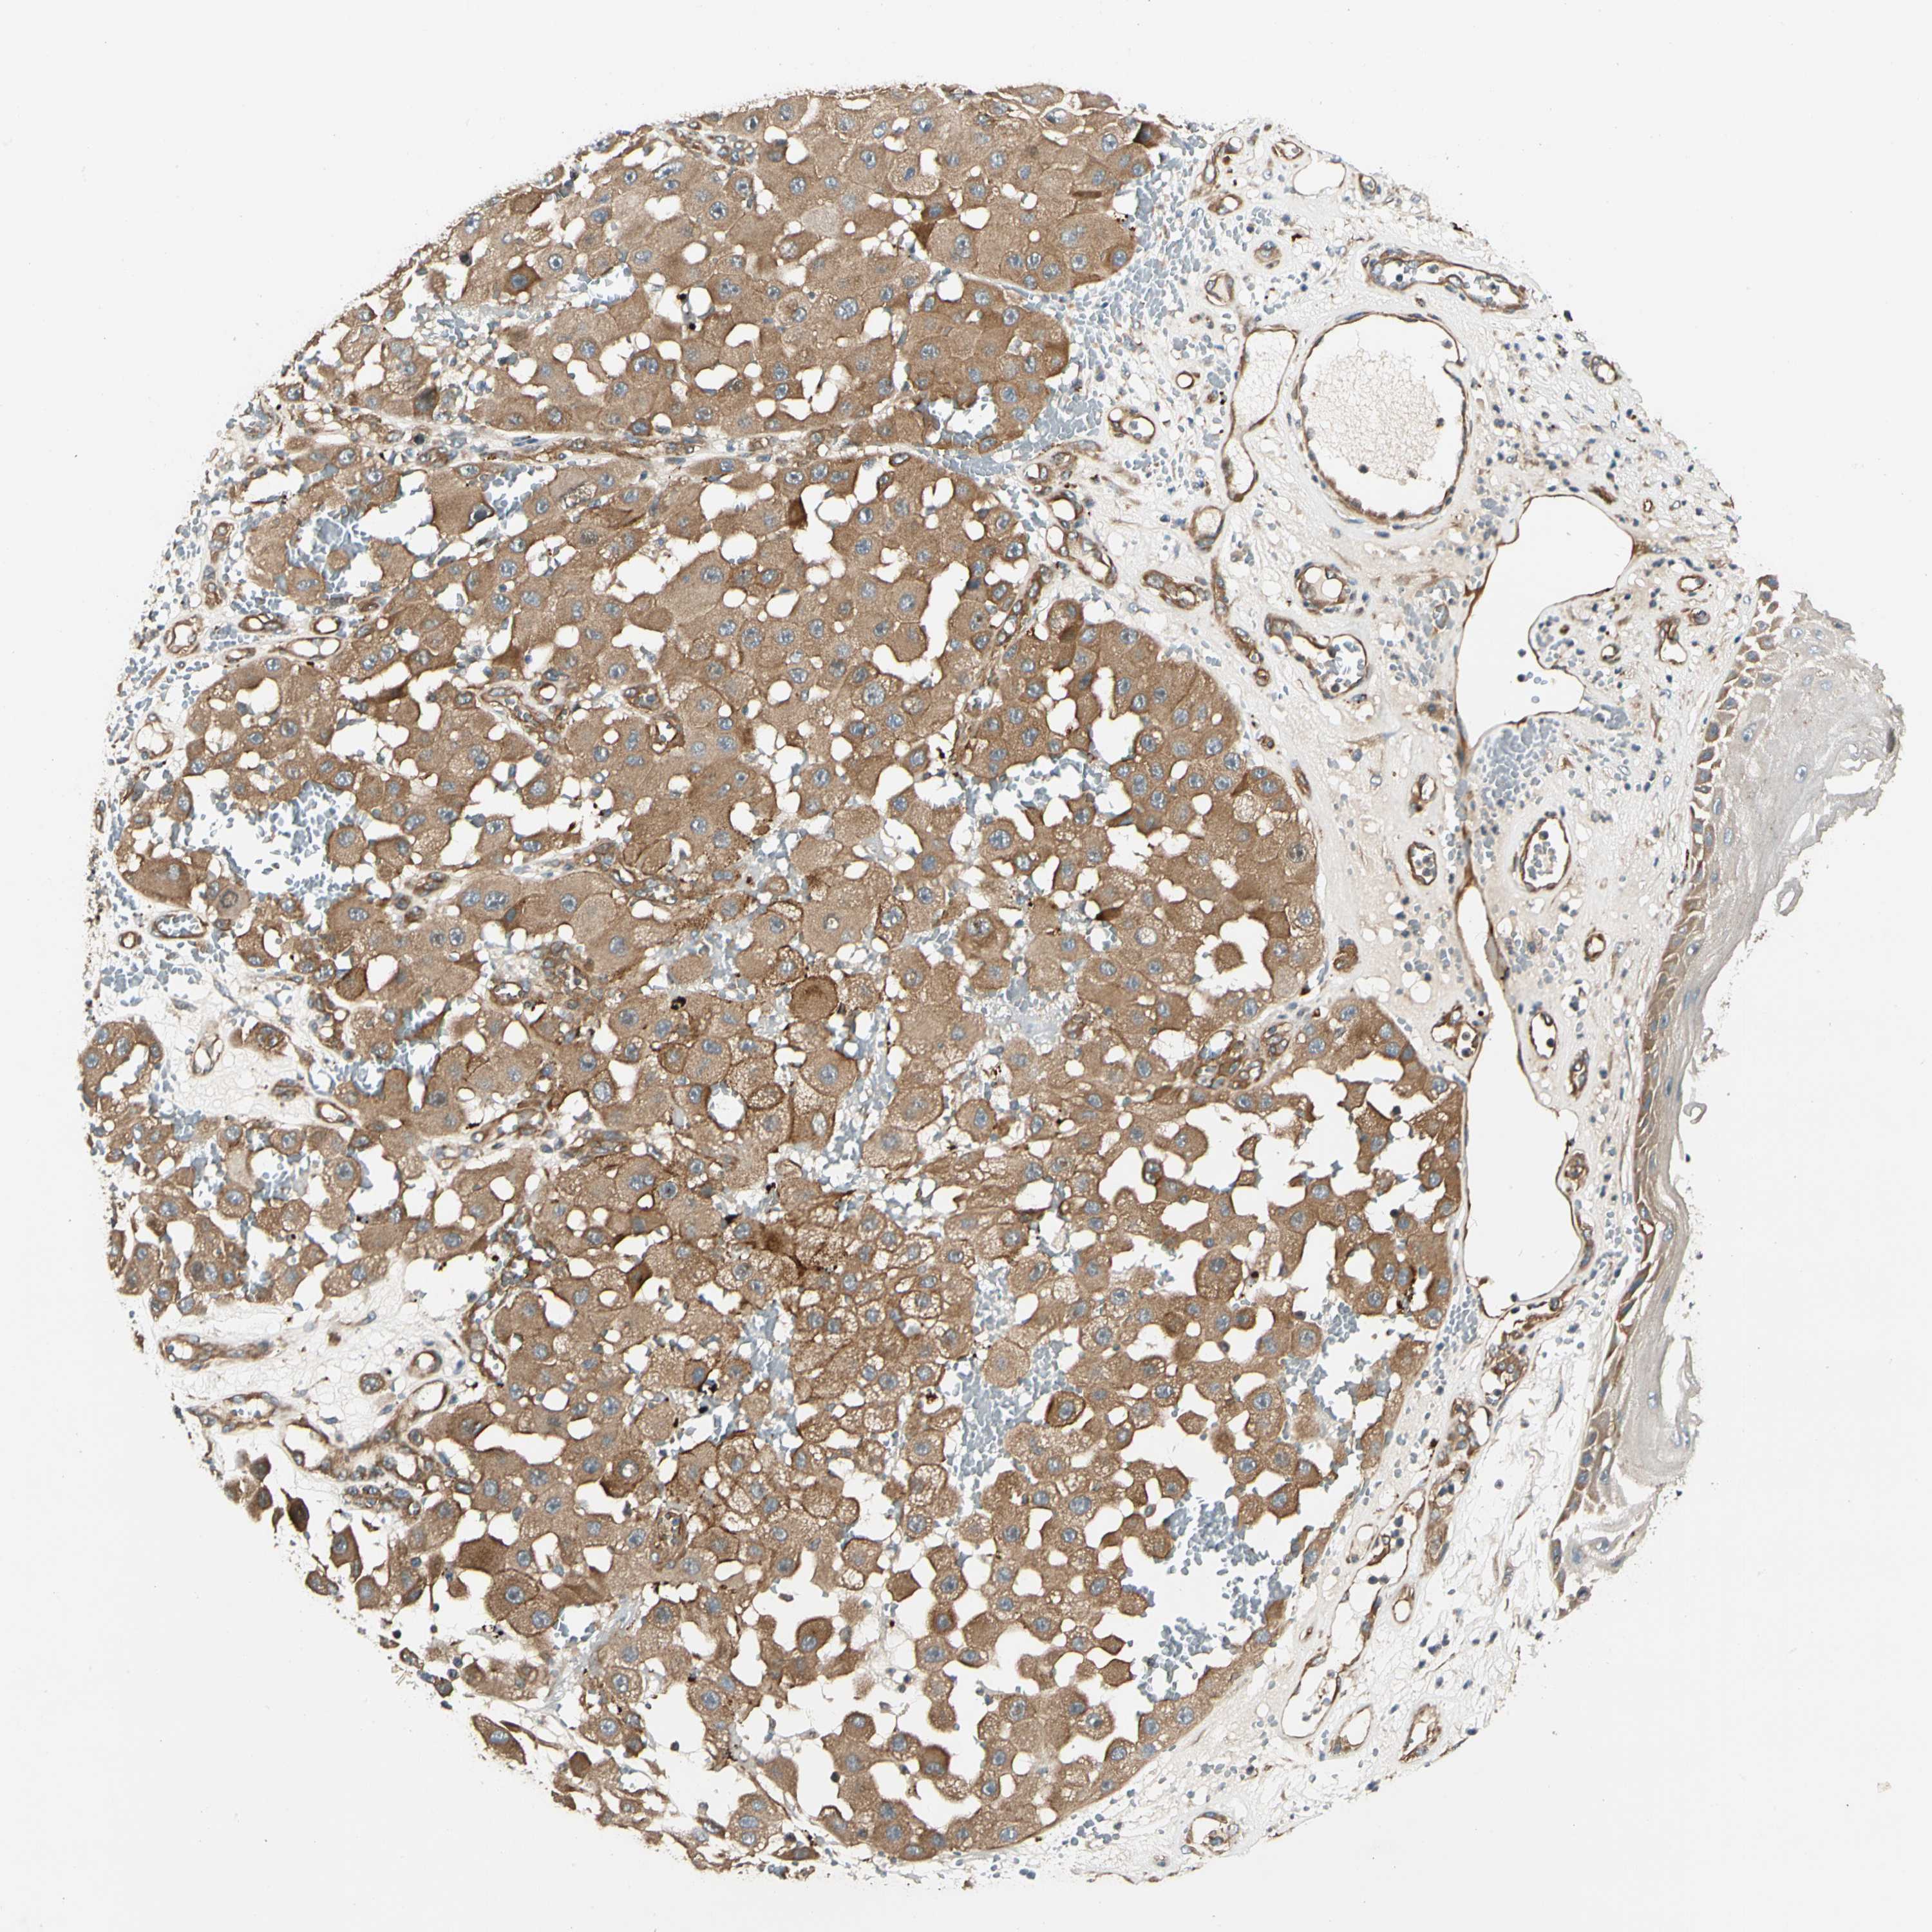

MELANOMA - Protein expressioni

A mouse-over function shows sample information and annotation data. Click on an image to view it in a full screen mode. Samples can be filtered based on level of antibody staining by selecting one or several of the following categories: high, medium, low and not detected. The assay and annotation is described here.

Note that samples used for immunohistochemistry by the Human Protein Atlas do not correspond to samples in the TCGA dataset.

Antibody stainingi

Antibody staining in the annotated cell types in the current human tissue is reported as not detected, low, medium, or high, based on conventional immunohistochemistry profiling in selected tissues. This score is based on the combination of the staining intensity and fraction of stained cells.

Each image is clickable and will lead to virtual microscopy that enables deeper exploration of all samples and also displays staining intensity scores, fraction scores and subcellular localization as well as patient and tissue information for each sample.

Antibody HPA007459

Antibody CAB008666

Staining

High

Medium

Low

Not detected

Intensity

Strong

Moderate

Weak

Negative

Quantity

>75%

75%-25%

<25%

None

Location

Nuclear

Cytoplasmic/membranous

Cytoplasmic/membranous,nuclear

Malignant melanoma, NOS

Malignant melanoma, Metastatic site